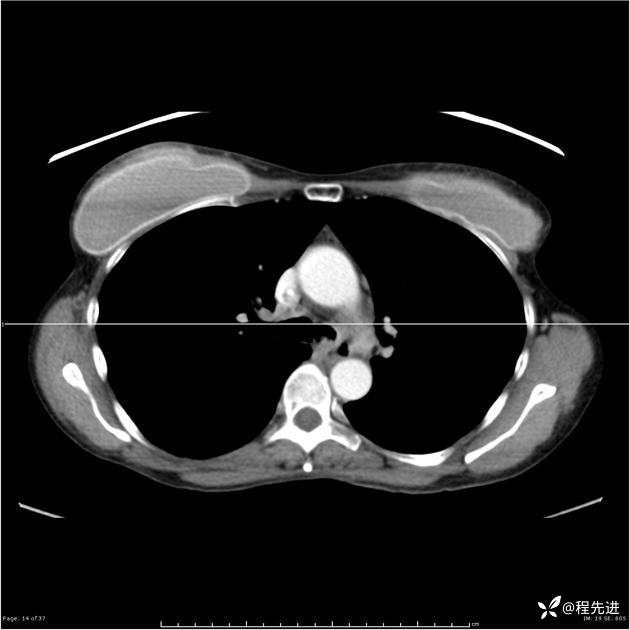

病例女,53岁,气管、左主支气管、下叶支气管内结节,乳头状瘤?期待你的精彩解读

女,53岁

乳头状瘤?